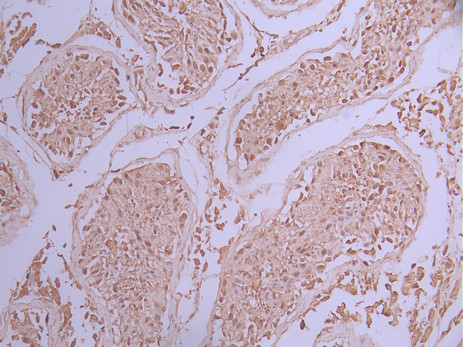

IHC image of CSB-RA035034A0HU diluted at 1:100 and staining in paraffin-embedded human lung cancer performed on a Leica BondTM system. After dewaxing and hydration, antigen retrieval was mediated by high pressure in a citrate buffer (pH 6.0). Section was blocked with 10% normal goat serum 30min at RT. Then primary antibody (1% BSA) was incubated at 4°C overnight. The primary is detected by a Goat anti-rabbit polymer IgG labeled by HRP and visualized using 0.05% DAB.

IHC image of CSB-RA035034A0HU diluted at 1:100 and staining in paraffin-embedded human testis tissue performed on a Leica BondTM system. After dewaxing and hydration, antigen retrieval was mediated by high pressure in a citrate buffer (pH 6.0). Section was blocked with 10% normal goat serum 30min at RT. Then primary antibody (1% BSA) was incubated at 4°C overnight. The primary is detected by a Goat anti-rabbit polymer IgG labeled by HRP and visualized using 0.05% DAB.